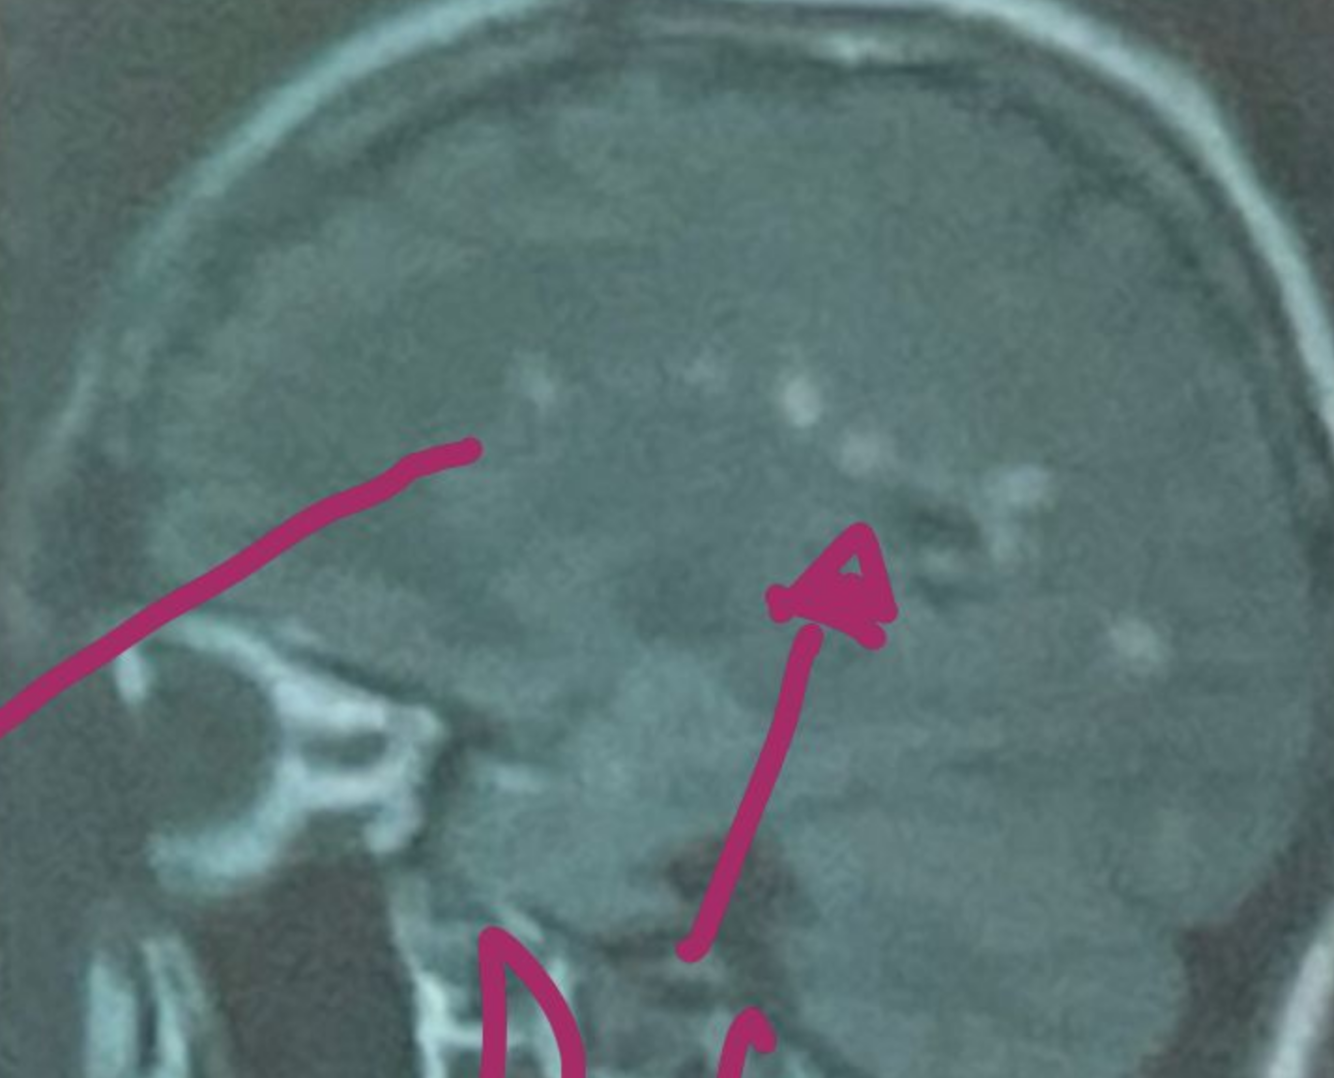

Esta resonancia corresponde a ADEM/EM

EM

ADEM

En la resonancia magnetica la esclerosis multiple da estos signos:

Hiperintensidad en T2 y FLAIR

Hipointensidad en T1

Lesiones redondas y ovaladas, bordes definidos menores a 5mm